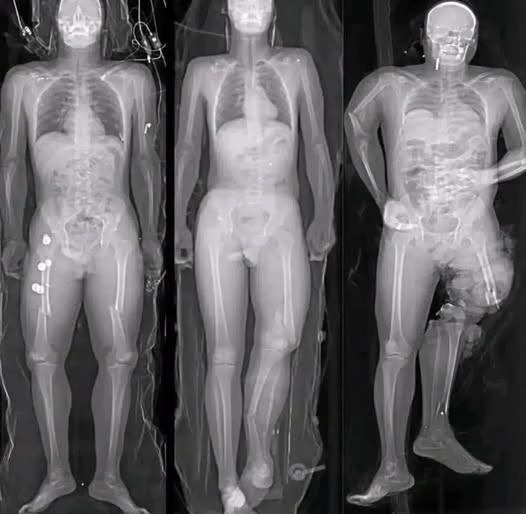

in recent months, a wave of alarming images and short messages has circulated widely across social media platforms, often accompanied by phrases such as “If you got the COVID vaccine, you should know this.” Many of these posts feature dramatic visuals—most notably illustrations of syringes aimed directly at the human heart—designed to provoke fear and urgency. While the images are striking, they rarely provide verified medical context. Instead, they rely on emotional reaction rather than evidence.For many people, these messages resurface lingering anxieties from the pandemic years. Even as daily life has largely returned to normal, uncertainty about health decisions remains an easy target for viral misinformation. Understanding what is factual, what is exaggerated, and what is simply false is essential for making informed decisions and avoiding unnecessary distress.

The success of these viral messages lies in how they are constructed. Fear-based imagery has always been effective at capturing attention, especially when combined with incomplete or vague warnings. A syringe aimed at a heart immediately suggests danger, even before a viewer reads any accompanying text. This technique taps into a natural instinct to protect oneself from harm.